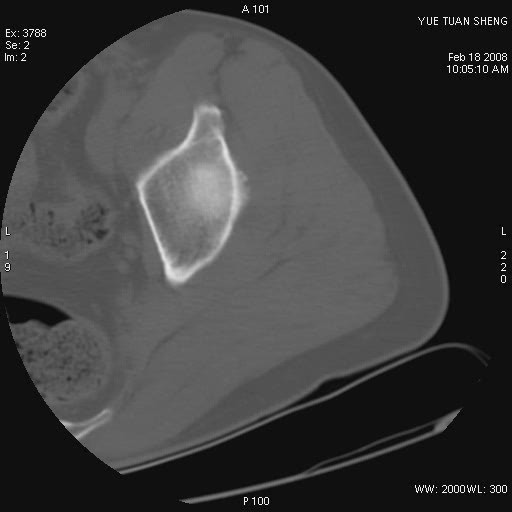

患者,男,56岁,左髋部疼痛1个月,x线:左股骨头高密度影,性质待定,右侧正常。左髋ct如图

左股骨颈区椭圆形磨玻璃样影,边缘明显硬化环环绕,其内见斑点状类钙化高密度影考虑 良性骨病-----骨纤,骨化性纤维瘤,内生软骨瘤。